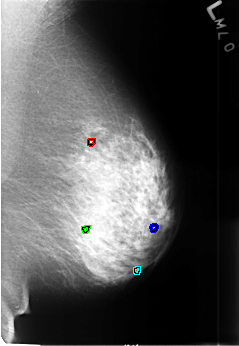

B_3449_1.LEFT_MLO

FILE: B_3449_1.LEFT_MLO.OVERLAY

TOTAL_ABNORMALITIES 4

ABNORMALITY 1

LESION_TYPE CALCIFICATION TYPE ROUND_AND_REGULAR-LUCENT_CENTERED DISTRIBUTION N/A

ASSESSMENT 2

SUBTLETY 3

PATHOLOGY BENIGN_WITHOUT_CALLBACK

TOTAL_OUTLINES 1

BOUNDARY

ABNORMALITY 2

ABNORMALITY 3

ABNORMALITY 4

TOTAL_OUTLINES 2